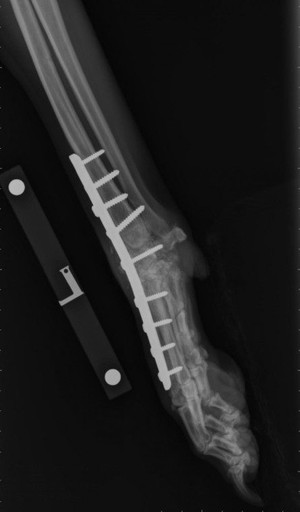

Pantarsal Arthrodesis

This procedure is a complete fusion of the ankle joint where all joint surfaces are removed of cartilage, bone graft filled into these spaces, then the ankle held in a standing angle with a bone plate/screws. Pantarsal Arthrodesis eliminates the need for the Achilles tendon.

It is a more aggressive procedure undertaken when tendon reconstruction has failed or if tendon reconstruction is not desired due to the potential for failure or long recovery time. Initially, the stabilization is protected with a splinted bandage or cast for 6-8 weeks. Exercise restrictions continue for a total of 12-14 weeks to allow complete fusion before return to normal activity.

Pancarpal/Pantarsal Arthrodesis

A complete arthrodesis involves fusion of the entire joint, eliminating all range of motion. A complete arthrodesis is necessary when the tibiotarsal or radiocarpal joints are affected. The cartilage is removed between all joints within the wrist or ankle then filled with bone graft. A specialized bone plate and screws are used to stabilize the bones until they fuse completely.